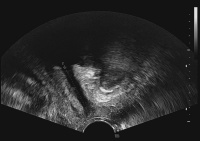

Kongressbericht: Belastungsinkontinenz - Individuell behandeln dank optimaler Diagnose. Aktuelle patientenspezifische Therapiekonzepte in der operativen Therapie der Belastungsinkontinenz. 14. und 15. Juni 2010, Wien

Journal für Urologie und Urogynäkologie 2010; 17 (3) (Ausgabe für Österreich): 51-53 Journal für Urologie und Urogynäkologie 2010; 17 (3) (Ausgabe für Schweiz): 50-52 Volltext (PDF) Abbildungen